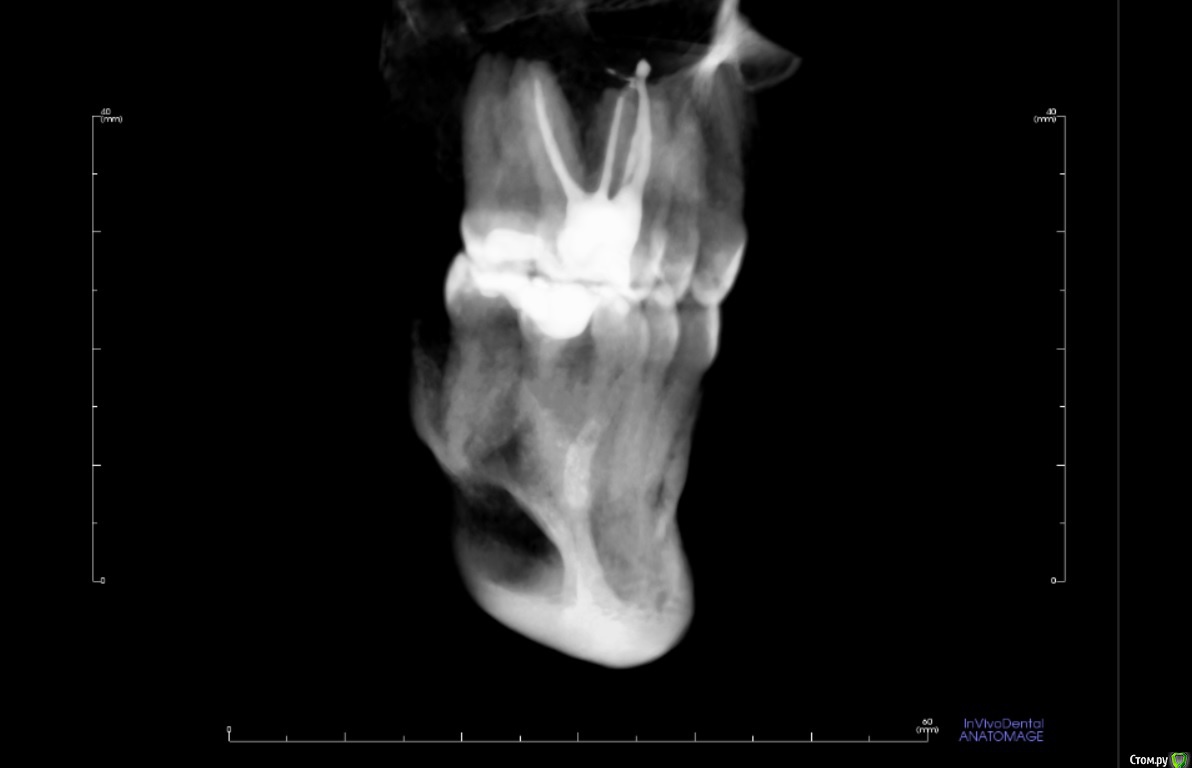

usilitel Опубликовано 4 декабря, 2018 Поделиться Опубликовано 4 декабря, 2018 (изменено) 10 месяцев назад депульпировали верхнюю 6-ку, с тех пор мучаюсь неврологическими симптомами (онемение, давление, зуд). На снимке с зубом всё нормально. Возможная причина - небольшое количество материала вышло в гайморову пазуху (но осталось под слизистой). Я думаю что этот материал мог задеть нерв, отсюда и симптомы. Зуб вырывать врачи отказываются, т.к. показаний к удалению нет. К тому же может не помочь.Хочу вынуть материал из гайморовой пазухи, но непонятно как это сделать. Прошу совета.Возможный варианты:1) Оставить всё как есть. Меня этот вариант не устраивает, т.к.: 1) материал может быть причиной проблем с неврологией, и его удаление может решить проблему. 2) зуб все равно рано или поздно придется удалять, не хотелось бы чтобы после удаления зуба в организме осталось инородное тело.2) Вынуть эндоскопом сверху. ЛОР сказал что так сделать нельзя, т.к. поскольку материал под слизистой - сверху его не увидишь. Правда можно содрать слизистую и всё-таки достать материал, но вред от такого действия многократно превысит пользу.3) При удалении зуба вынуть материал снизу. По словам хирурга - стоматолога - это сделать нереально, т.к. для этого придется разрезать перегородку, отделяющую гайморову пазуху, и она потом сама не заживёт.4) Надеяться, что матерал сам выйдет вместе с зубом при удалении зуба. Вариант крайне маловероятный, т.к. при удалении зуба материал практически наверняка останется в пазухе.5) Распломбировать канал, протолкнуть материал дальше в гайморову (чтобы он вышел за слизистую), а потом вынимать сверху эндоскопом. Не уверен что найду терапевта который согласится это сделать.6) Сразу после удаления зуба протолкнуть материал дальше в гайморову (чтобы он вышел за слизистую), а потом вынимать сверху эндоскопом. Не уверен что найду хирурга который согласится это сделать. PSЗуб мне не жалко, всё равно рано или поздно его надо будет удалять. Изменено 4 декабря, 2018 пользователем usilitel Ссылка на комментарий

usilitel Опубликовано 6 декабря, 2018 Автор Поделиться Опубликовано 6 декабря, 2018 выкладываю снимки Ссылка на комментарий